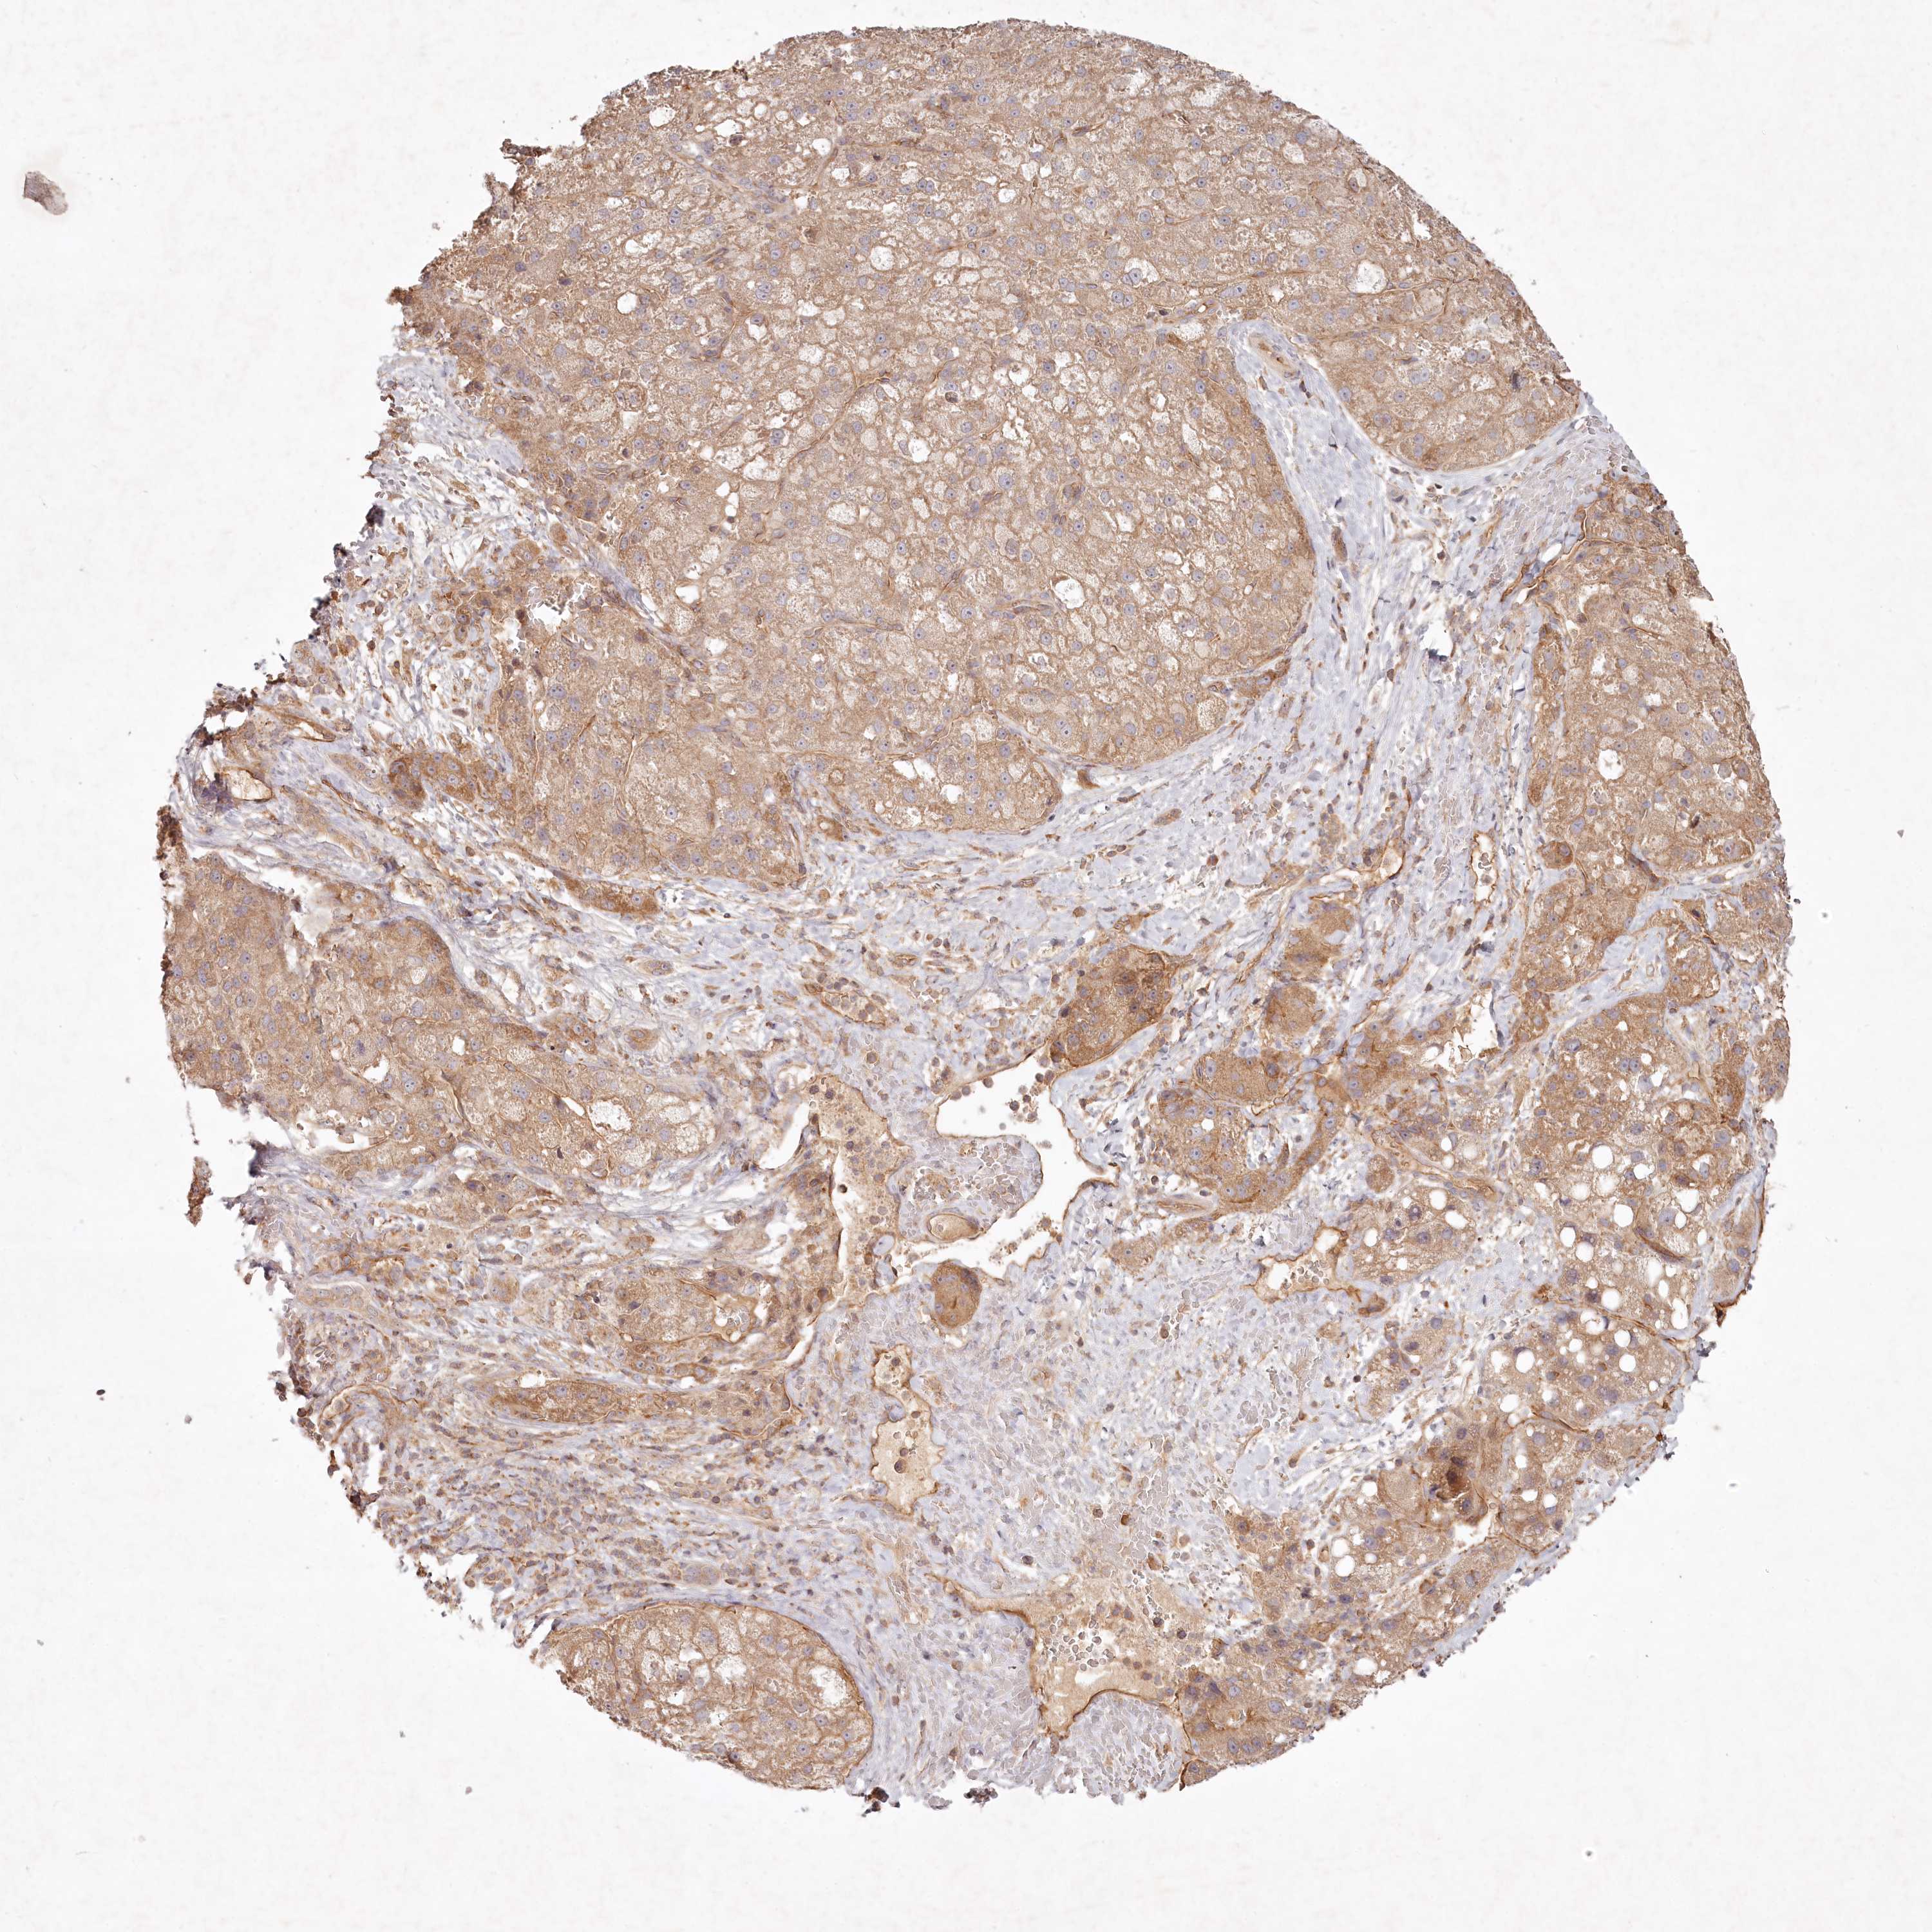

LIVER CANCER - Protein expressioni

A mouse-over function shows sample information and annotation data. Click on an image to view it in a full screen mode. Samples can be filtered based on level of antibody staining by selecting one or several of the following categories: high, medium, low and not detected. The assay and annotation is described here.

Note that samples used for immunohistochemistry by the Human Protein Atlas do not correspond to samples in the TCGA dataset.

Antibody stainingi

Antibody staining in the annotated cell types in the current human tissue is reported as not detected, low, medium, or high, based on conventional immunohistochemistry profiling in selected tissues. This score is based on the combination of the staining intensity and fraction of stained cells.

Each image is clickable and will lead to virtual microscopy that enables deeper exploration of all samples and also displays staining intensity scores, fraction scores and subcellular localization as well as patient and tissue information for each sample.

Antibody HPA038298

Staining

High

Medium

Low

Not detected

Intensity

Strong

Moderate

Weak

Negative

Quantity

>75%

75%-25%

<25%

None

Location

Nuclear

Cytoplasmic/membranous

Cytoplasmic/membranous,nuclear

Cholangiocarcinoma

Carcinoma, Hepatocellular, NOS